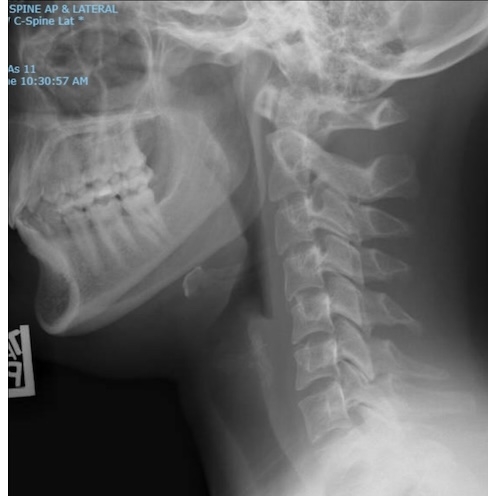

| Do Not Jump To Conclusions - Neck Pain After A High Ropes Course Mishap - Page #3 | |||